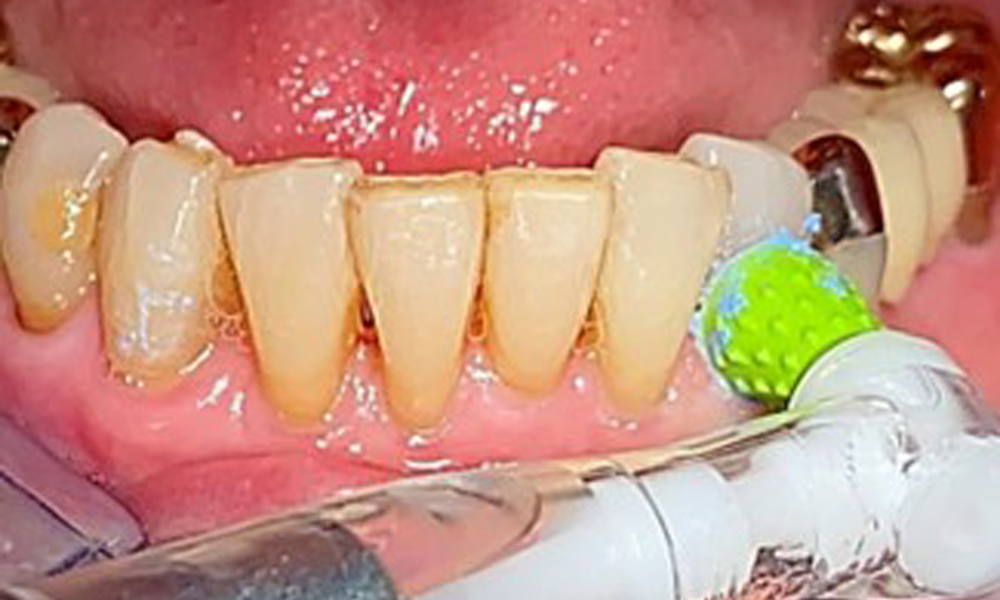

Специално за телескопичните протези се препоръчва еднократна четка (фиг. 8), а пациентът трябва да бъде посъветван за подходящия размер на интерденталната четка (фиг. 9). Пациентът изпълнява тези препоръки за интраорална хигиена у дома в продължение на много години и беше насърчен да продължи по време на професионалната профилактична среща с денталния лекар.

Илюстрация на еднократна четка за домашна грижа за имплантите и телескопичните протези.

Фиг. 8: Илюстрация на еднократна четка за домашна грижа за имплантите и телескопичните протези.